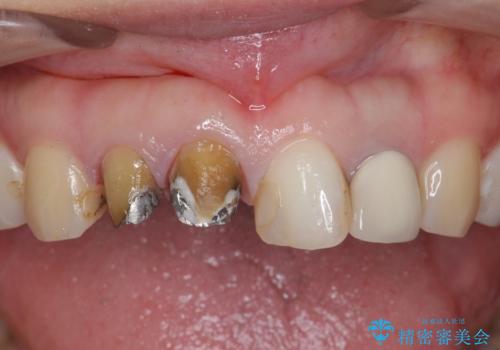

- 前歯を天然の歯のようにきれいにやりかえたいと希望され来院されました。

根尖病変の存在が判明したため、感染根管治療後にオールセラミックジルコニアクラウンを製作します。

- 37万円(仮歯×3・ファイバーコア×2・ジルコニアクラウン×3)費用は治療当時の料金となります